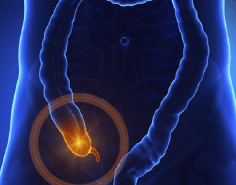

Apéndice

La apendicitis es el proceso inflamatorio agudo que se presenta en una estructura localizada en la primera porción del colon que se llama apéndice y la cual se produce por la obstrucción del orificio que comunica el apéndice con el colon, produciendo inflamación aguda de este órgano. Esta patología se manifiesta por dolor abdominal de inicio súbito y que conforme pasa el tiempo incrementa de intensidad llegando a ser incapacitante, acompañándose de nausea, vómito, fiebre, falta de apetito. El tratamiento es quirúrgico y el diagnóstico temprano previene el desarrollo de complicaciones graves que ponen en riesgo la salud del paciente.

El realizar la cirugía por Laparoscopía genera grandes beneficios ya que el realizarla mediante mínima invasión disminuye el dolor después de la cirugía, reduce el riesgo de infección de heridas, permite una incorporación más rápida a sus actividades. Contamos con amplia experiencia en la atención de esta patología, lo cual permite diagnosticar oportunamente y tratarla con la mejor tecnología disponible, lo cual reduce al máximo las complicaciones y permite una recuperación rápida de los pacientes.